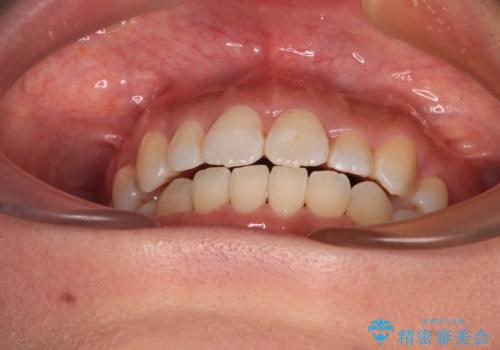

- 上下前歯のデコボコを気にして来院された患者様です。

右上と左下の小臼歯が1本ずつ欠損しており、奥歯の咬み合わせが乱れている状態でした。

バランスを取るために右下と左上の小臼歯を1本ずつ抜歯し、移動のための固定源としてアンカースクリューを利用してワイヤー装置による矯正治療を行うこととしました。

骨格的な左右差があり、上下正中をぴったり合わせることは難しく、奥歯の咬み合わせの調整にも時間がかかりましたが、きれいに整えることができました。